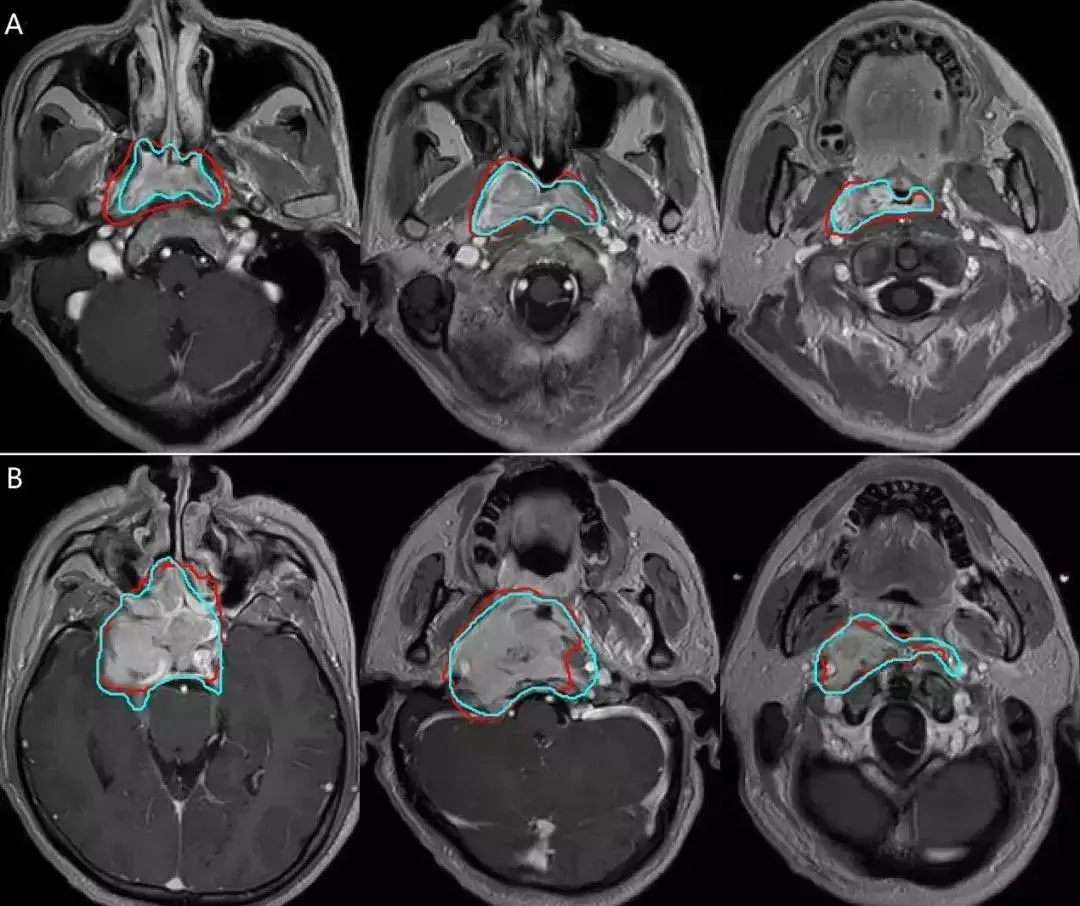

肿瘤影像与放疗之头颈鼻咽癌

中山肿瘤联合视见科技和港中大实现鼻咽癌放疗靶区人工智能自动勾画